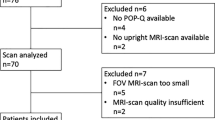

Two symptomatic patients were excluded (unable to follow instructions during the MRI exam and incomplete exam n = 1, failure to return the questionnaire and undergo urogynecologic examination for POP-Q grading n = 1). The final population comprised 23 consecutive premenopausal patients with symptomatic POP and 22 asymptomatic premenopausal nulliparous volunteers. Baseline characteristics of the patients and volunteers are depicted in Table 1.